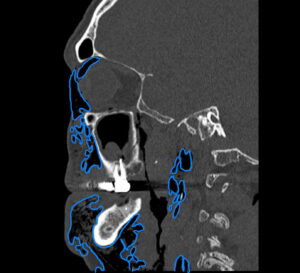

Dental Free Air CT Sagitial Annotated. JETem 2025